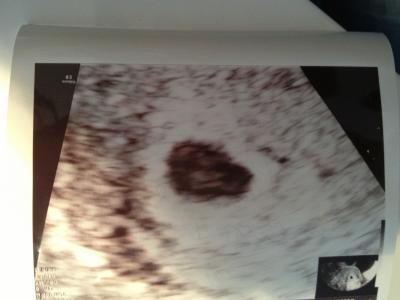

Hallo da ich jetzt zum 3 mal im KH war vor lauter Angst das ich wieder eine FG habe ist heute herausgekommen das meine FH on 0,47cm am 22.12 auf heute 27.12 auf 0,82cm gewachsen ist, ob das jetzt gut ist weiß ich nicht :( ( bin jetzt 5+6ssw) Wie sieht das bei euch aus.....leider konnte man nur eine Verdickung an der einen seite sehen ....und was pulsieren ( der Arzt meinte es könnte ein eckhocker sein Der pulsierende fleck könnte auch von mir ausgelöst worden sein weil ich so aufgeregt war..... muss jetzt bis zum 7.1.13 warten bis ich zu meinem Termin bei meiner FÄ kann!!! Zeigt her eure US Bilder !!!

Bild zu US ..... was sieht man bei euch? - Forum für August - Mamis